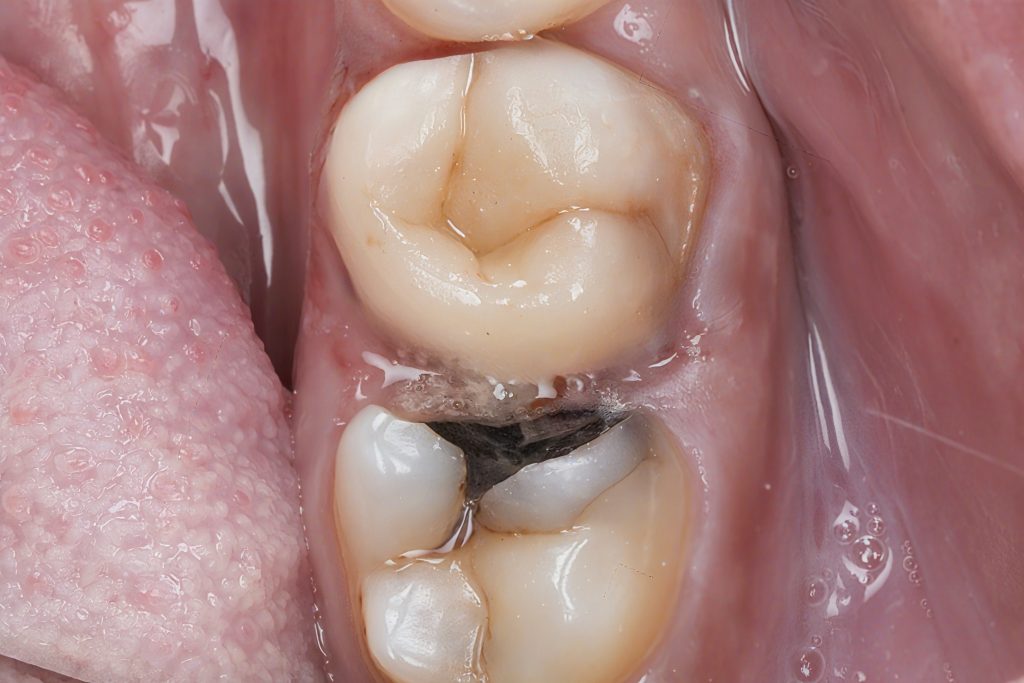

C. Deep Margin Elevation (Two-Step DME)

The cervical margin was subcrestal, making isolation and adhesive bonding impossible without DME.

Step 1 – Cervical Sealing

- Flowable resin composite placed as gingival seat

- Adapted with transparent matrices for tight cervical adaptation

- Objective: seal the dentin and block fluids from the sulcus

Step 2 – Final Elevation

- Layer of packable composite built to bring the margin supra-gingival

- Margin finished to crisp enamel to enable predictable bonding for final restoration

Why DME?

- Preserves the tooth

- Avoids crown lengthening surgery

- Maintains periodontal biology

- Creates a clean, accessible, bondable margin

This technique is well validated for MOD, deep proximal, and subgingival lesions.